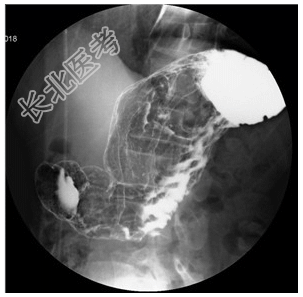

- [材料题] 男性,55岁。反复黑便1月。行X线检查。

- 简答题1、患者的诊断及依据是什么?

- 简答题2、鉴别诊断有哪些?